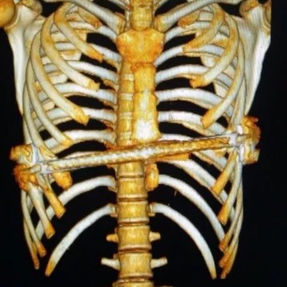

Incisions were made along the previous surgical scars on both sides of the chest wall to remove the bars placed during the Nuss procedure. Then, the cyst on the left anterior chest wall was explored and incised through the incision on the left side of the chest wall, and the contents of the abscess were thoroughly debrided. A third incision along the midline scar allowed careful pre-shaping of the depressed bony structure of the anterior chest wall. Two bars were then implanted to complete the Wung procedure. Postoperatively, the chest wall appearance was restored to normal.

2. Improper bar Placement and Positioning: Preoperative imaging reveals that the bar was positioned along the upper edge of the groove-like depression and was placed at an angle.For optimal support and effective correction of the depressed bony structure, the bar should have been positioned at the base of the depression.

3. Insufficient Number of Bars: In adult patients, the larger chest wall depression and increased bone density generally necessitate the use of at least two bars during corrective surgeries to ensure adequate support and achieve the desired outcome. However, only one bar was used in the patient’s initial surgery, which was insufficient to effectively correct the depression.